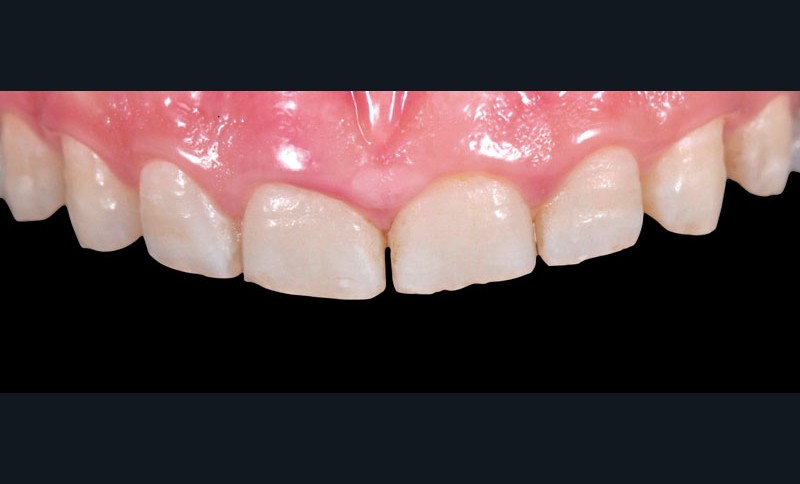

L’analyse clinique (fig. 1 à 7)

Dans les cas d’usure, le repositionnement des futurs bords libres des 2 incisives centrales par ajout de composite à main levée…